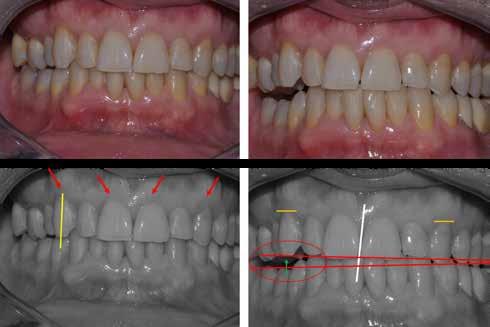

A fogászati kezelések során manapság már nem kizárólag az esztétikai megjelenés helyreállítására törekszünk. Sokszor a kedvezőtlen esztétikai megjelenés hátterében álló okok következményes módon a fogazat funkcionális működését is károsítják, így a kezelések során ezeknek a helyreállításával is foglalkoznunk kell. A különböző funkcionális és esztétikai diszkrepanciák kezelésére számtalan módszer létezik, ám ezen fogászati beavatkozások mindegyikében közös, hogy a kivitelezésük során nagyon szoros együttműködésre van szükség a kezelést végző fogorvos és a munkáját segítő fogtechnikus között. Az alábbi esetbemutatás során egy fiatal hölgypáciens fogazatának héjak alkalmazásával történő esztétikai és funkcionális rehabilitációját szeretnénk ismertetni.

sára is szükség van (2. és 4. ábra).

A 19 éves hölgypáciens azzal a kéréssel jelentkezett a rendelőnkbe, hogy szebb fogakat szeretne. Az első konzultáció alkalmával megkérdeztük, hogy mi zavarja leginkább a fogazatának jelenlegi megjelenésében, valamint azt is megbeszéltük vele, hogy milyen végeredmény elérése esetén lenne maradéktalanul elégedett. Ebben az esetben a kezelési célokat az alábbiakban határoztuk meg:

A páciens fogazata esztétikai megjelenésének és funkcionális működésének a lehető legtöbb, saját foganyag megtartása mellett történő helyreállítása (1. és 3. ábra).

A lehető legideálisabb esztétikai végeredmény elérése érdekében néhány esetben a fogak alakjának módosítá -

A kezelés megtervezése során kifejezett jelentősége van annak, hogy jó kommunikáció legyen a páciens, a fogorvos és a fogtechnikus között. A páciens leendő fogazatának természetes megjelenését a kezelésben részt vevő team szakmai felkészültsége, gyakorlati tapasztalata és a kezelés sikerességének irányába történő elkötelezettsége biztosítja. A beavatkozások megkezdése előtt megtörtént a páciens anamnézisének a felvétele, valamint a klinikai kivizsgálását is elvégeztük. Ezt követően lenyomatokat készítettünk a kiindulási állapotról, majd a kiindulási helyzetet extra- és intraorális fotók segítségével is rögzítettük (13. a-c. ábra).

A kezeléstervezés egyik legfontosabb lépése a mock-up elkészítése. A mock-up alapjául szolgáló wax-up-ot (felviaszolás) is ugyanolyan részletességgel kell a fogtechnikusnak elkészíteni, mintha azok már a végleges fogpótlások alapjául szolgáló mintázatok lennének. A mock-upnak nagyon pontosan kell illeszkednie, valamint a tervezett fogpótlás meg-

jelenését is rendkívül élethűen kell reprezentálnia. Ahhoz, hogy a páciens mock-uppal kapcsolatos első benyomásai kedvezőek legyenek, a mock-up színének a páciens „szemfehérjének” színével meg kell egyeznie. A kezelési cél páciens által történő elfogadása és a tervezett eredménnyel kapcsolatos „wow-effektus” kialakulása nagyban függ a páciensben az első megtekintés során kialakult első benyomásoktól.

Az eddigi tapasztalataink szerint a páciensek jelentős többsége egyértelműen kifejezi az elégedettségét, ha a mock-up megfelel az eredeti elképzeléseiknek. A bemutatásra kerülő esetben is ez történt. A tervezett végeredmény megtekintését követően a páciens azonnal kérte az általunk javasolt kezelési tervben ismertetett beavatkozások elvégzését. A héjak alapanyagául az Ivoclar Vivadent által gyártott A1-es színű Telio CS kerámiát javasoltuk. Az anyagválasztás hátterében az állt, hogy ez az anyag nagy keménységgel rendelkezik, valamint az, hogy a felszínét nagy simaságúra lehet polírozni. A páciens rendkívül fiatal életkora is azt a terápiás koncepciót erősítette, hogy a kezelés során lehetőség szerint kizárólag non-invazív beavatkozásokat alkalmazzunk.

A kezelés során az jelentette a legnagyobb kihívást, hogy a héjakkal ellátott fogak élethűen utánozzák a természetes fogazat megjelenését. A fogpótlás színének, valamint a restaurátumok felszíni textúrájának és alakjának harmonikusan kell a páciens arcesztétikájához és karakteréhez illeszkednie.

A tényleges protetikai ellátás megkezdése előtt a páciens mosolygás közben látható fogait otthoni fogfehérítés keretei között a kérésének megfelelő A1-es fogszín eléréséig fehérítettük. A fehérítés során a későbbiekben héjakkal ellátásra kerülő fogak színén nem változtattunk. A fogak előkészítése részeként csupán a két felső nagymetsző (1.1,2.1) incizális élét kellett kismértékben redukálni. A többi felső front fog (1.3,1.2,2.2,2.3) nem került preparálásra.